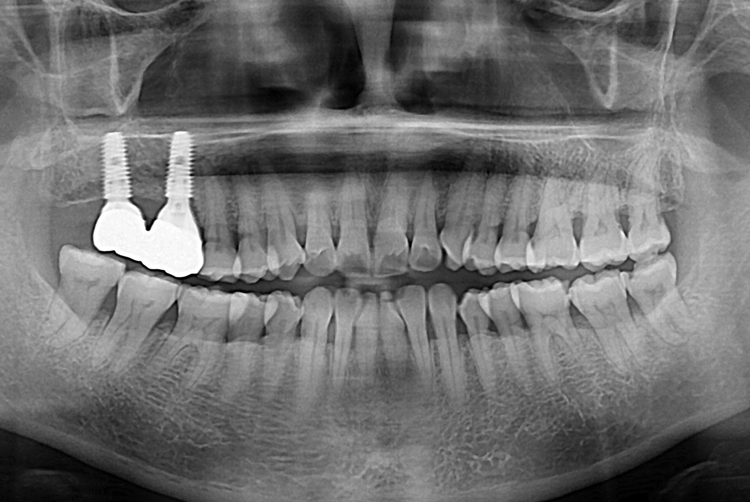

[임플란트] 어금니 임플란트

치료후 : 2019-06-26

세종치과는 많은 환자와 다양한 케이스를 바탕으로

항상 편안한 임플란트 수술을 제공하고자 노력하고,

오래동안 튼튼히 쓸 수 있는 임플란트 수술을 가장 큰 목표로 삼고 있습니다.